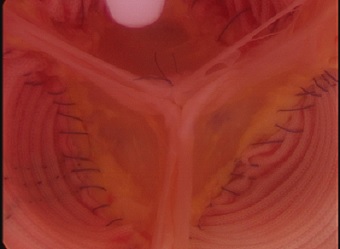

大動脈弁閉鎖不全症に対して、積極的に行ってきた自己弁温存基部置換術を含む大動脈弁形成は、術中大動脈内視鏡テスト(Aortoscopy)を行うことで精度の高い長期の予後が期待できる大動脈弁形成となりました。

人工弁を使わない大動脈弁形成が70歳以下では標準術式として行っています。

2尖弁術後

3尖弁術後